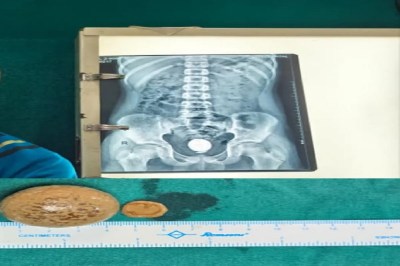

मरीज के मूत्राशय से निकाली गई पथरी।

Ahmedabad: चिकित्सकों ने एक किशोर के मूत्राशय से लगभग 90 ग्राम वज़न और 4 सेंटीमीटर आकार की पथरी निकाली। विशेषज्ञों का कहना है कि बच्चों में इतनी बड़ी पथरी का बनना अत्यंत दुर्लभ है। सामान्यतः छोटे बच्चों में मूत्राशय की पथरी 1-2 सेंटीमीटर तक ही होती है और लक्षण दिखते ही उपचार कर दिया जाता है। लेकिन इस मामले में पथरी इतनी बड़ी हो गई कि मरीज को लंबे समय तक तकलीफ़ सहनी पड़ी। महानगरपालिका संचालित एल.जी. अस्पताल के जनरल सर्जरी विभाग के चिकित्सकों ने यह सफल सर्जरी की।सर्जरी विभाग के डॉ. तपन शाह ने बताया कि मरीज को पेशाब में जलन, रुक-रुक कर पेशाब आना, ठंड लगना और बुखार जैसे लक्षणों के साथ ओपीडी में लाया गया था। जांच में मूत्राशय में दो पथरियां मिलीं जो लगभग 4 सेंटीमीटर और 2 सेंटीमीटर की थी। एक्स-रे और सोनोग्राफी रिपोर्ट से स्पष्ट हुआ कि बड़ी पथरी पूरे मूत्राशय में फैली हुई थी। मूत्राशय की पथरी खतरनाक होती है क्योंकि यह पेशाब की नली को ब्लॉक कर सकती है, जिससे मरीज को इमरजेंसी में लाना पड़ता है। कभी-कभी पेट से नली डालनी पड़ती है और किडनी फेल होने का भी खतरा रहता है। इस मामले में ऑपरेशन कर पथरी को सुरक्षित रूप से निकाल लिया गया।